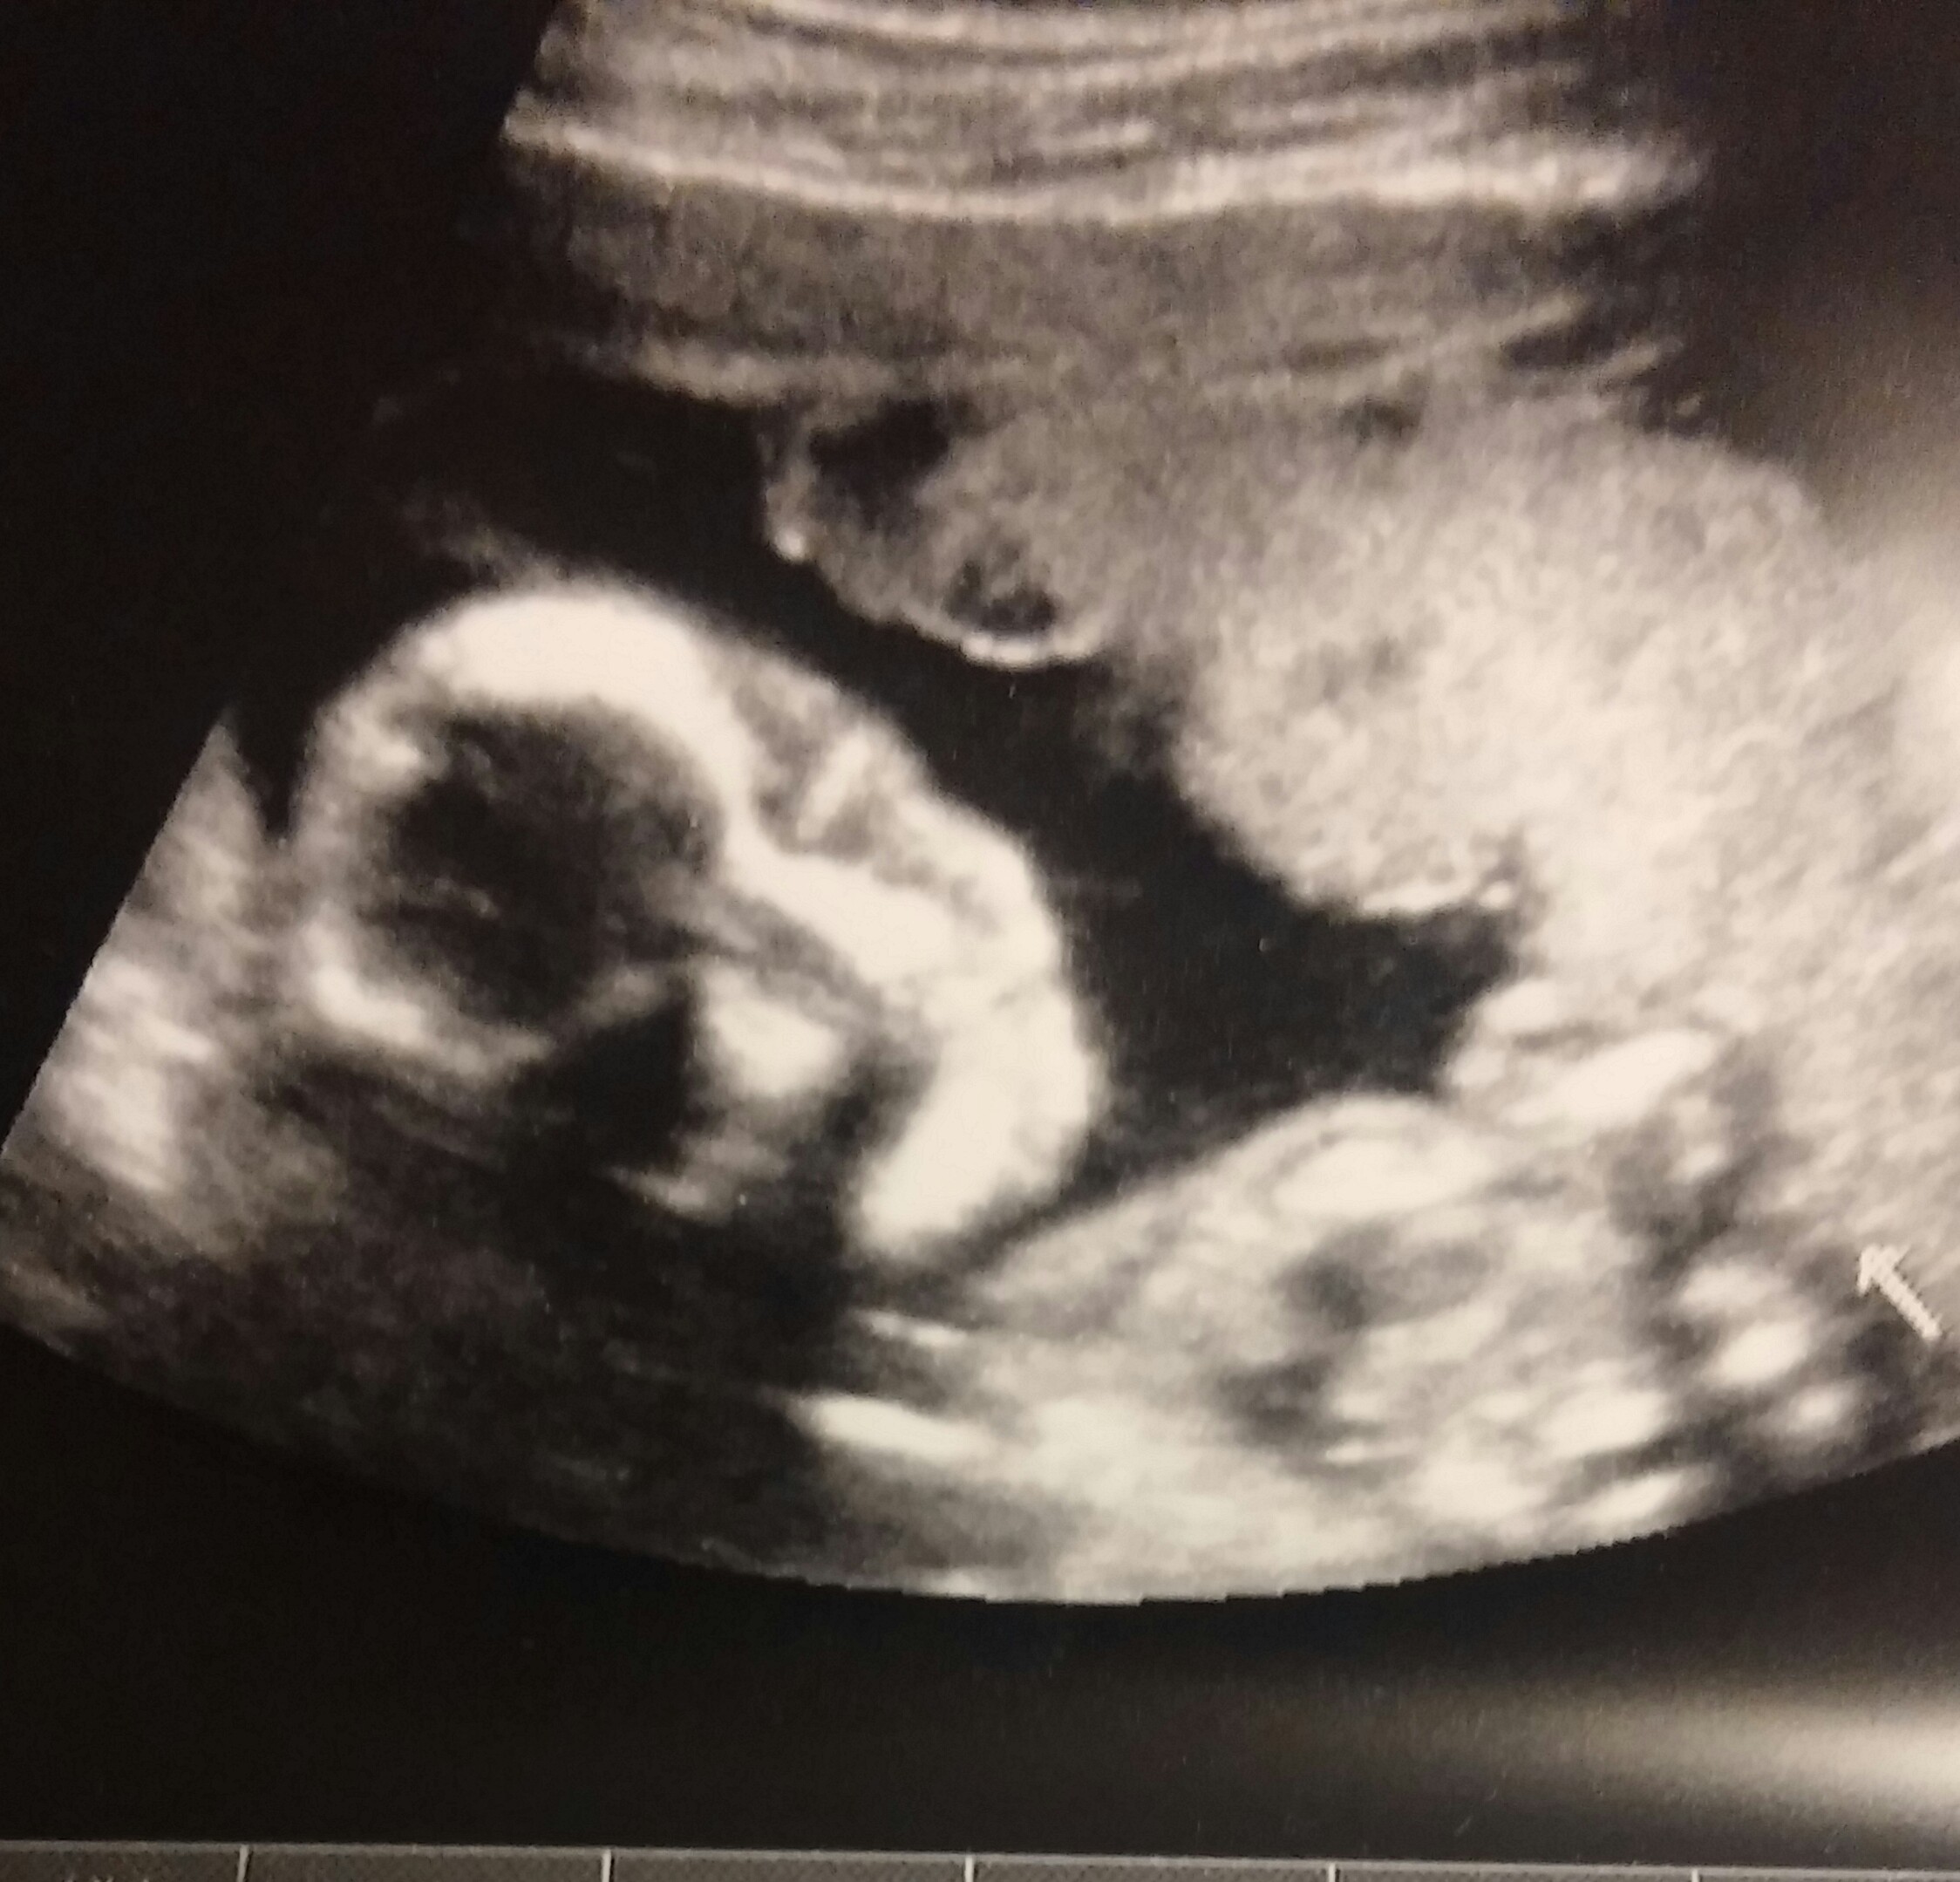

My a/s was traumatic, but all is well now and baby appears healthy. The pic is our 6 year old daughter on the left, and our current baby on the right, Vivienne Rose!